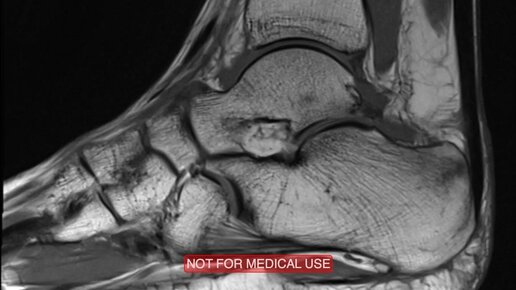

Что покажут снимки МРТ голеностопного сустава (видео)